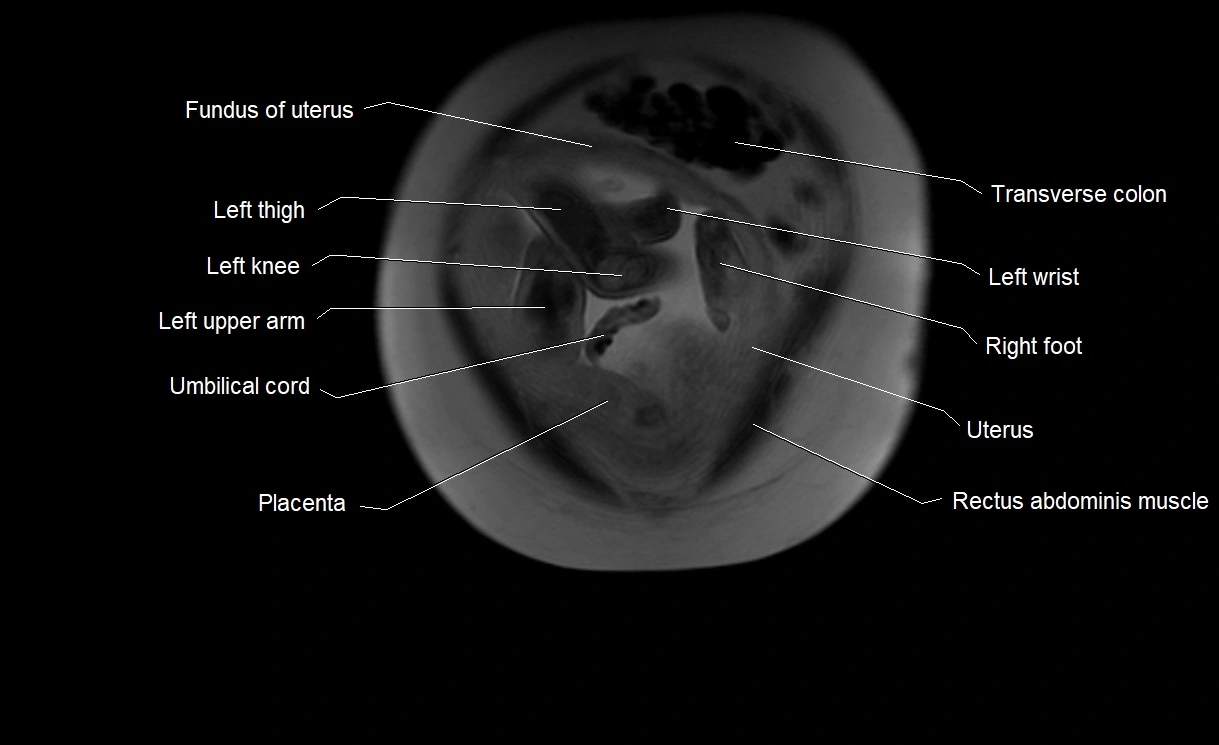

Amniotic fluid

Amniotic fluid is the protective liquid surrounding the fetus within the amniotic sac. It plays an essential role in cushioning the fetus, enabling fetal movement, maintaining temperature stability, and allowing for normal lung and musculoskeletal development.

The volume and composition of amniotic fluid change throughout pregnancy. It is mainly derived from maternal plasma in early pregnancy, while in later stages, it consists largely of fetal urine, lung secretions, and transmembrane exchanges.

• Surrounds and cushions the developing fetus

MRI Appearance

T2 HASTE (T2 GRE):

• Amniotic fluid shows very bright hyperintense signal

• Provides natural contrast against fetus and placenta

• Small particles (vernix) may appear as scattered hypointense foci within bright fluid

T1 GRE:

• Amniotic fluid shows low signal intensity (dark)

• Hemorrhage, infection, or proteinaceous content may cause focal or diffuse high signal intensity